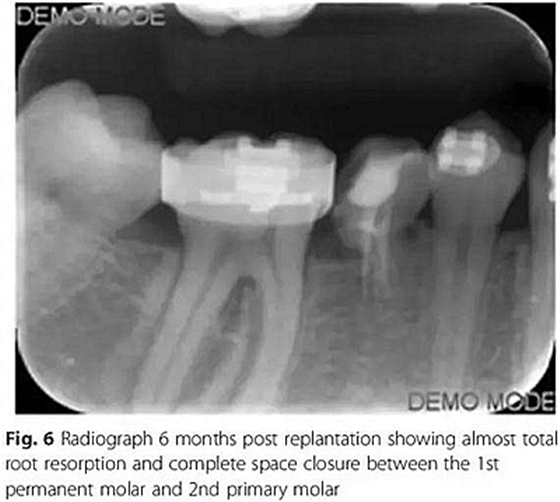

第6個月,臨床和影像檢查顯示乳牙幾近完全的替代性牙根吸收和間隙的完全關閉。最終,將乳磨牙拔除并開始進行完整的正畸治療。在接下來一年,用0.017’’*0.025’’末端回彎的不銹鋼弓絲和彈性牽引剩余間隙關閉,并以II類牽引作為支持。